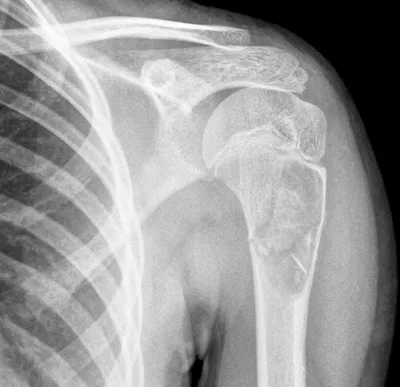

Shoulder glenohumeral arthrogram

ShoulderArthrogramInterventional+1

4/23/2026